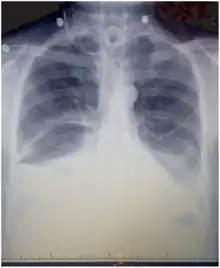

Chest X-ray showing bilateral chylothorax

Chest X-rays can detect a chylothorax. It appears as a dense, homogeneous area that obscures the costophrenic and cardiophrenic angles. Ultrasounds can also detect a chylothorax, which appears as an echoic region that is isodense with no septation or loculation. However, neither a normal chest x-ray nor an ultrasound can differentiate a chylothorax from any other type of pleural effusion.[1]